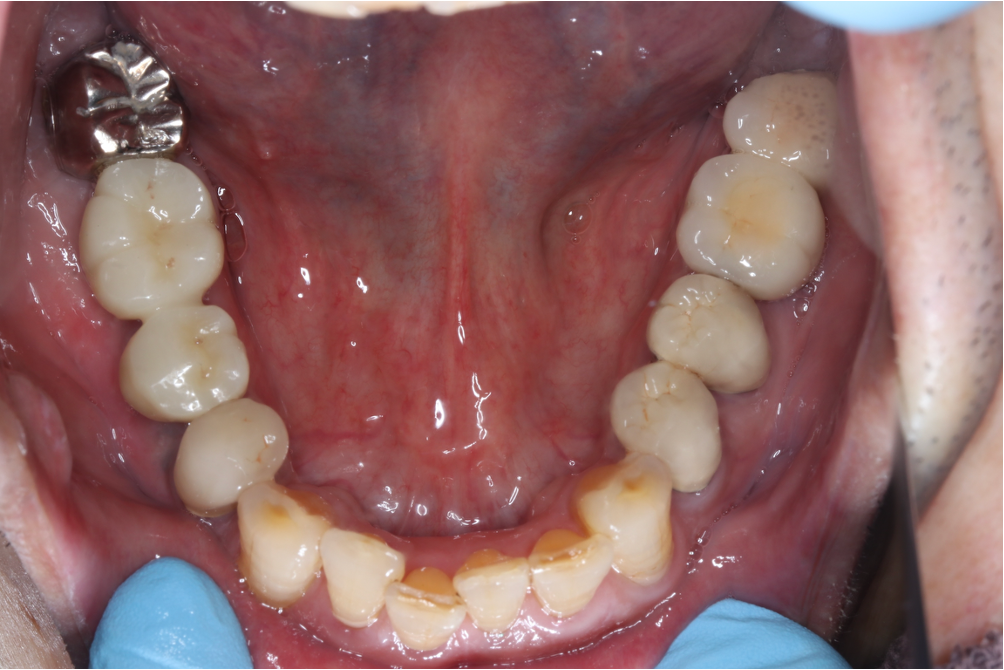

インプラント症例③

年齢 50代女性

治療期間 4ヶ月

インプラントメーカ ストローマンインプラント

治療内容 カスタムアバットメント、上部ジルコニア

治療箇所 左下5番、6番 右下6番、7番

治療費用 1,600,000円